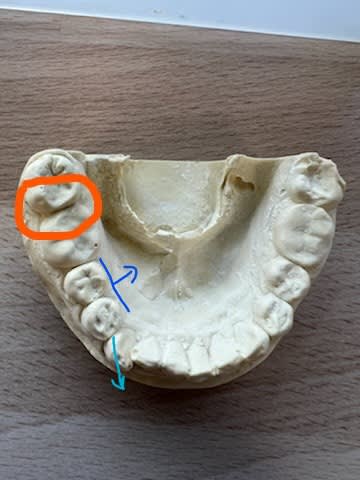

Pour quelle raison la crête mesiale de la 47 est elle aussi saillante ?

Dur d'être certain du fait des autres soins présents, mais ce serait pas une 8 en place de 7?

Une couronne ou une restau ?

Faut quand même lui mettre un coup de bzzbzz sur la crête,pour qu'elle n'accroche plus en incision/propulsion.

Sur la pano, on a plus l’impression que c’est la crête distale de la 46 qui est absente.

Ben clairement, c'est une casserole toute plate, mais en général les crêtes s'alignent quand même toute seules.

(une coiffe réalisée avant 12 ans, qui aurait guidé la 7 dans cette drôle de position lors de son évolution?)

(d'ailleurs elle est même pas si plate sur le modèle. )

Tu noteras la facette d'usure monstrueuse en mésial de 47, j'étais persuadé qu'il y aurait une restauration à la radio, vu la différence en comparaison des sillons conservés en distal.

Le point de départ hypothétique c'est la couronne sur 46 qui aurait entrainé une distoversion de la 47.

Ce qui a projeter dans le plan de l'occlusion la crète mésiale de la 47 créant une interférence.